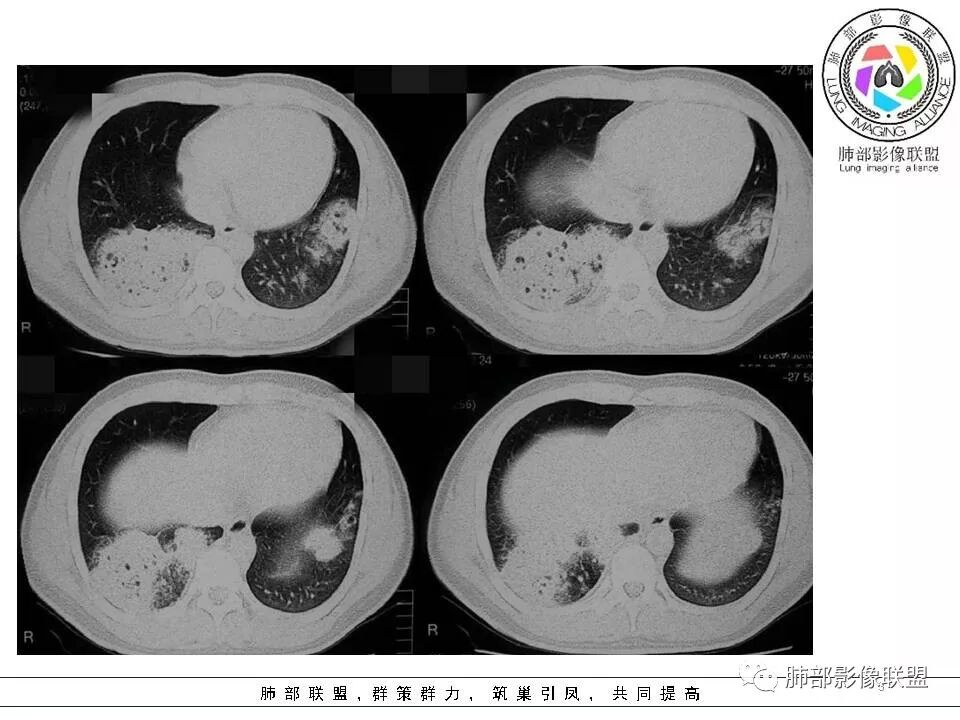

病例二

病灶的形态与分布如何?

右肺中叶及下叶大片实变影及双肺多发腺泡结节,局部成簇的腺泡结节融合成片,以外围及胸膜下分布为主

病灶的走行情况如何?

磨玻璃结节沿支气管飘散并落脚其他肺叶和肺段

病灶边缘情况如何?

以膨隆为主,局部稍平直、收缩

病灶内支气管情况如何?

支气管走形僵直、狭窄、中断,分支减少,呈“枯树枝”改变(图1-4红色短箭头)。可惜没有增强,不能了解病灶强化及血管情况。

病灶内的坏死情况?

有少许小空泡,未见明显液化坏死

周围肺野情况如何?

周围肺野有边界清楚GGO,局部中轴间质明显增厚并呈结节样改变(图1绿色箭头),树芽征不明显

老年男性,有发热、咳嗽、咳少量浓痰,呼吸困难,临床病程不详,但是影像上有实变、簇状分布的腺泡结节及枯树枝征,老年男性,高度怀疑肺炎型肺癌;肺炎型肺癌的病理基础是癌细胞沿肺泡壁、小叶中心、腺泡腔成簇、匍匐性生长,并沿肺泡孔及支气管播散,并且癌细胞分泌粘液引起肺组织实变,液化坏死少见,而干酪性肺结核多有虫噬样空洞及液化坏死区,结核支气管多为壁增厚 、扩张,肺癌的支气管多为狭窄堵塞、粗细不均。

温馨提示:病例2病理结果细支气管肺泡癌此定义取消,现归为腺癌,也是肺炎性肺腺癌的主要类型之一。详细内容请参考肺部影像联盟文章“不同时期腺癌的病理影像诊断”。